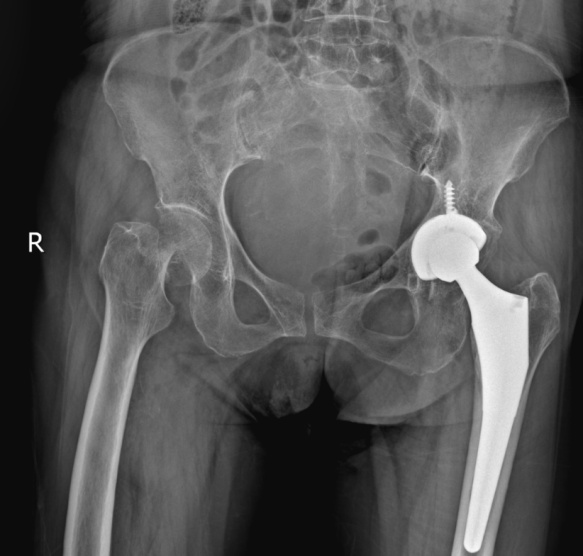

前来就诊时,徐奶奶的家人回忆,老人活动时不慎摔倒,右边髋部着地,当时她感觉髋部有剧烈疼痛,不能活动。在家中休息一段时间后,疼痛迟迟无法缓解,于是来到方塔中医医院骨伤科就诊。接诊医师经过仔细问诊、查体及影像学检查后,诊断徐奶奶为右股骨颈骨折,且断端错位。

为此,团队想到了人工髋关节置换。其中,人工股骨头置换(半髋)较人工全髋关节置换手术时间更短,出血量更少,手术可以在麻醉医师团队的配合下进行局部麻醉,可以降低高龄患者的麻醉风险和手术意外,具有一定优势。此外,相较于股骨颈骨折空心钉内固定,术后患者不能下地负重行走,人工髋关节置换的患者则可以在术后早期、疼痛耐受的情况下进行地面活动,对于高龄患者是更优的手术方案,具有快速康复,减少术后并发症等优点。经过严密的讨论,手术团队最终制定了人工股骨头置换(半髋)的手术方案。

骨伤科团队与患者及其家属充分沟通病情,患者和家属同意接受手术治疗。手术团队仅用不到一个小时,顺利进行了右侧人工股骨头置换(半髋)术。目前,徐奶奶已康复出院。而在出院前,她已能够在助行器的辅助下进行走路练习,避免了骨折后因长期卧床引起的一系列并发症,对于改善创伤后的生活质量有很大帮助。